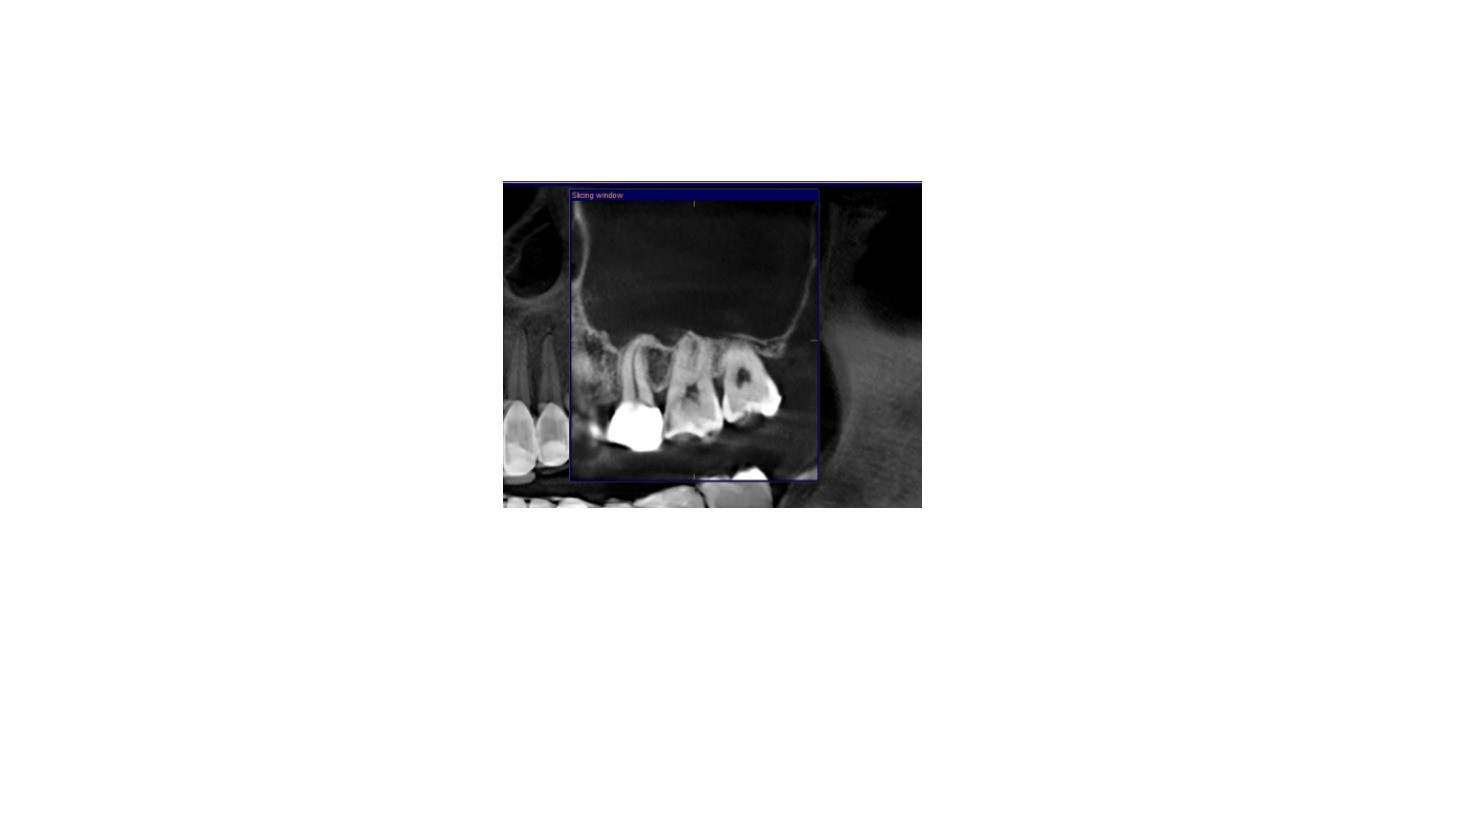

Sinusitis adalah peradangan pada rongga sinus, yaitu ruang-ruang berisi udara di dalam tulang wajah, seperti di sekitar hidung, dahi, dan pipi.